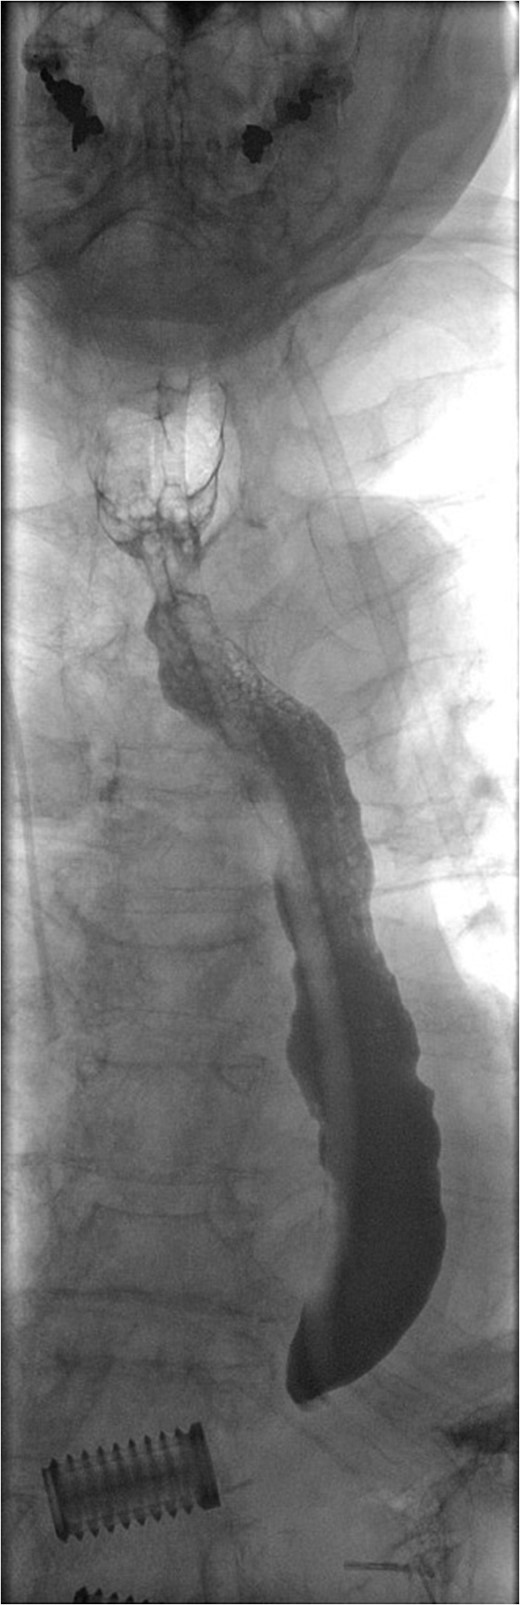

Fluoroscopic image demonstrating contrast entering intraperitoneal drain in proximity to gastric perforation (previous spinal surgery).

For management of this oesophageal perforation and definitive management of her gastric perforation, the patient was referred to the authors’ unit, a tertiary referral centre for upper GI surgery. In the first instance, a water-soluble contrast swallow was performed to assess the status of the oesophageal perforation. This demonstrated no leak of contrast (Fig. 3) and therefore a diagnostic endoscopy under general anaesthesia was performed in order to assess the cervical oesophagus and also the known gastric perforation. This endoscopy demonstrated a healed oesophageal perforation but persistent gastric perforation with established cavity (Fig. 4) containing an existing transabdominal Robinson drain. The cavity was felt to be of a size likely to heal without the need for further negative pressure vacuum therapy, so a T-tube was placed across it. The established track of the existing abdominal drain was used to guide placement of the T-tube. A nasojejunal feeding tube was placed under vision.

Water-soluble contrast swallow study demonstrating free flow of contrast from oropharynx to stomach with no evidence of leak.